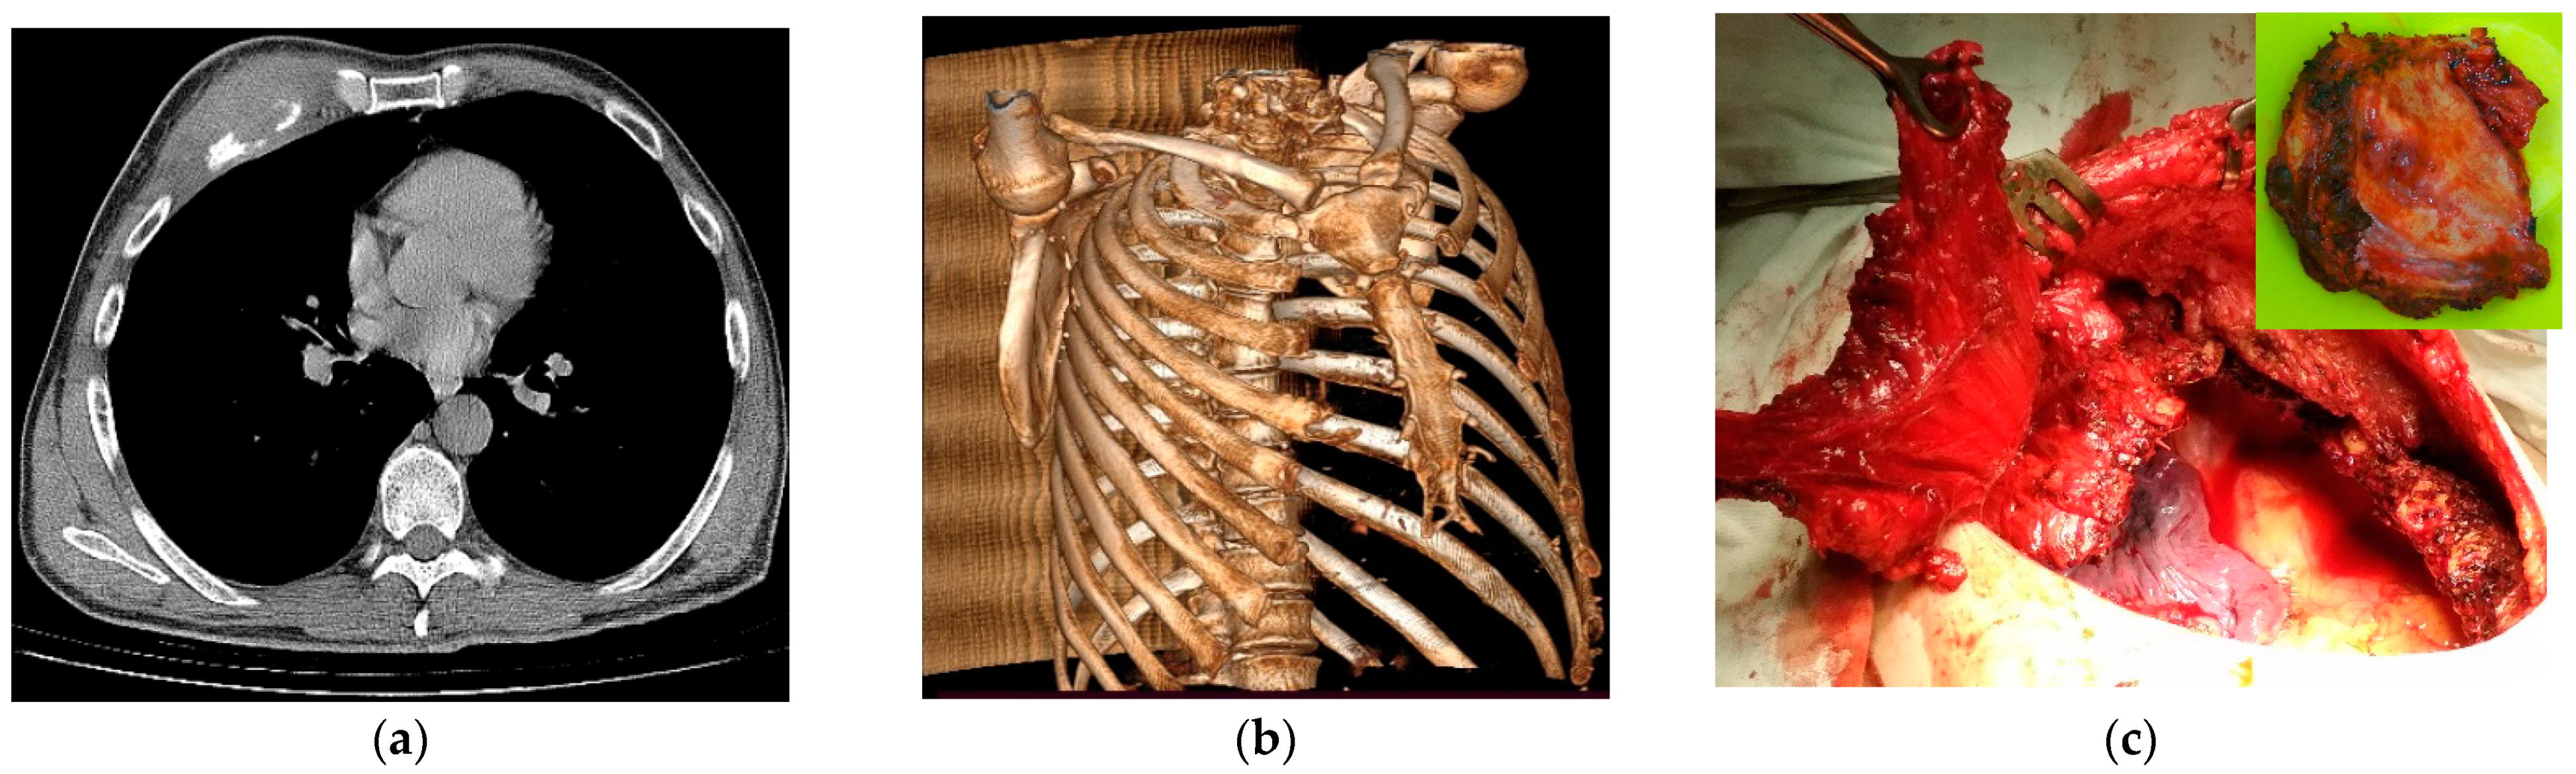

2. Materials and Methods

3. Results and Discussion